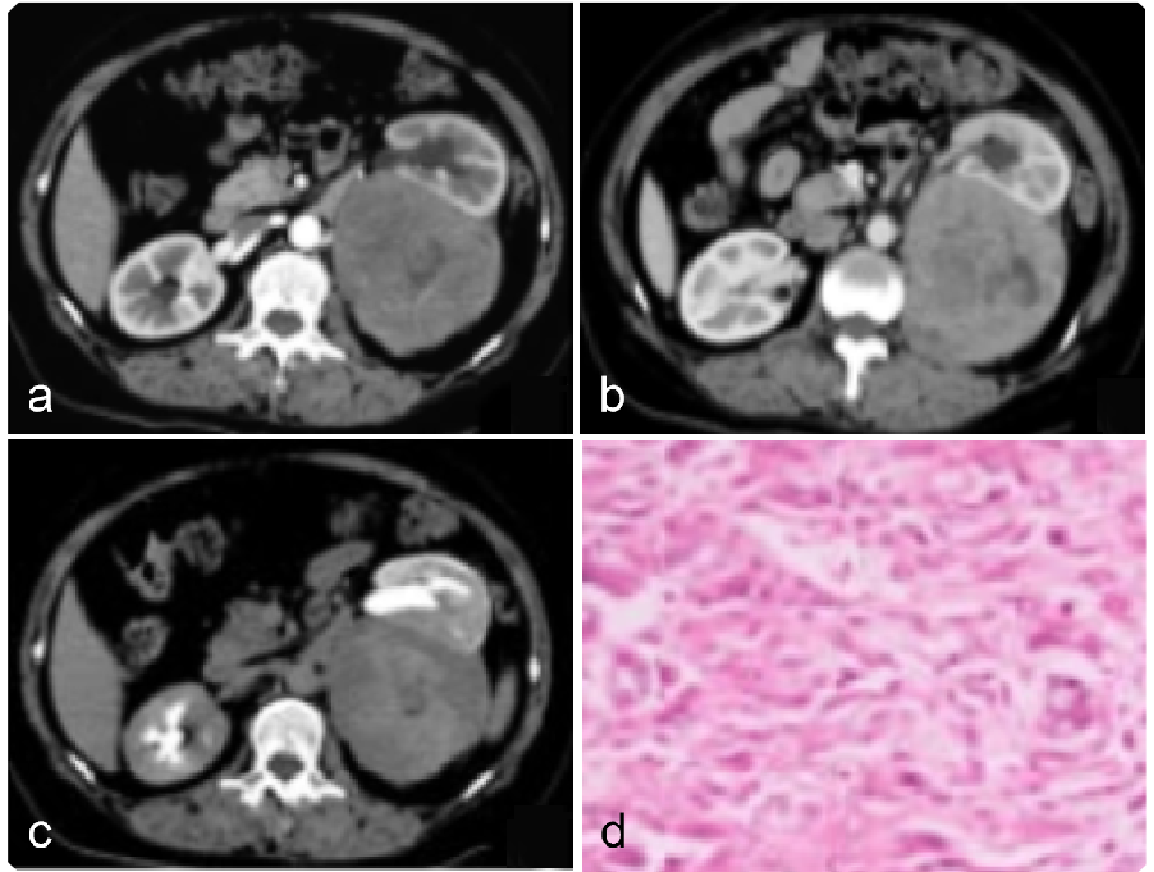

cc77276319006960e0db0009375aaf2d.png 病例 19:腹膜后多形性横纹肌肉瘤  60岁男性,因“左腰部肿块进行性增大1个月”人院。查体腰部无压痛,实验室检查无异常MRI平扫T1WI 肿块呈等-稍低信号(图a),T2WI呈不均匀明显高信号(图b),内可见囊变、坏死,未见出血;增强扫描肿块呈持续填充式强化,其内可见无强化区域(图c)。手术病理显示腹膜后肿物呈鱼肉样改变,质地较软,可见小出血灶及大片坏死;光镜下见肿瘤细胞弥漫分布,细胞大小不一,细胞核高度异型(图d)。免疫组织化学染色:SMA(+),Des(+),Myogenin(少许+),MyoD1(+),S-100(少许+),Ki-67(约30%+)。